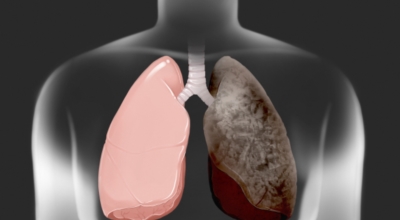

폐암의 공통 위험요소로 손꼽히는 이유가 되는 것으로 흡연이 있답니다. 흡연자는 비흡연자에 견주어 십몇 배는 더 폐암 발병확률이 높다고 하며 어느정도 기간 동안 흡연했는지에 따라 폐암 발생확률은 더더욱 더 높아져요. 흡연자라고 해도 금연을 하게 되면 폐암 발병확률이 가파르게 감소한다고 하니 폐암이 걱정되신다면 가장 먼저 금연은 필수입니다.

간접흡연 외에도 공사장과 같은 곳에서 미세먼지나 석면, 비소, 라돈, 카드뮴 등 신체에 옳지 않은 성분에 노출되는 환경적 요인으로 폐암이 발병할 수 있다고 하며 유전적 요인으로도 폐암이 발병할 수 있다고 해요. 가족 중 폐암을 앓았던 분들이 있다면 그렇지 않은 분들에 비교해 2배 가량 더 폐암에 걸릴 확률이 높다고 하는데요 이렇듯 폐암은 나도 모르는 새에 발병할 수 있으므로 자신의 신체 상태를 수시로 체크하여 폐암을 초기에 발견하는 것이 현명해요.